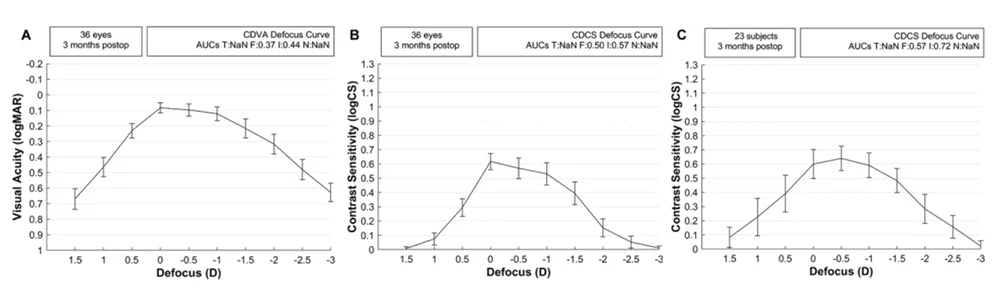

Defocus curve

Uiteraard moet ook ELON zich bewijzen wanneer het gaat over optische prestaties. Uit een recente studie van Fernandez et al. (JCRS, 2025)1 blijken onderstaande defocus curves:

- monoculaire defocuscurve van de gezichtsscherpte met beste correctie voor vertezicht (A);

- monoculaire defocuscurve van het contrastgevoeligheidsvermogen met beste correctie voor vertezicht (B);

- binoculaire defocuscurve van het contrastgevoeligheidsvermogen zonder correctie voor vertezicht (C).

De AUC’s komen overeen met de oppervlakten onder de curve, berekend voor het totale bereik [T], verte [F], intermediaire [I] en nabije [N] afstanden.